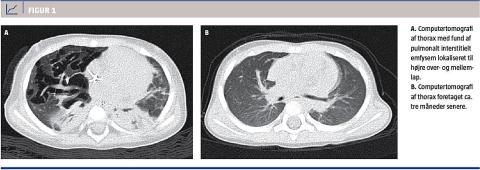

En 15 måneder gammel tidligere rask dreng blev akut indlagt efter syv dages anamnese med feber og vejrtrækningsbesvær. Den først målte iltsaturation var 60%. Pga. manglende effekt af iltterapi og continuous positive airway pressure blev der hurtigt påbegyndt respiratorbehandling. Det eneste positive mikrobiologiske fund var respiratorisk syncytialvirus påvist ved polymerasekædereaktion. Inden for to døgn udvikledes der bilateral pneumothorax, subkutant emfysem og pneumomediastinum, og på trods af dyb sedering, relaksering og ventilation med højt positive end expiratory pressure (12 cm H2O) var patienten ikke sufficient oxygeneret (PaO2 5,9 kPa), hvorfor overflytning til højt specialiseret enhed med henblik på extracorporal membrane oxygenation (ECMO) blev arrangeret. Imidlertid bedredes tilstanden efter overflytningen og start af inhalation med nitrogenoxid og lungeprotektiv ventilation i form af high frequency oscillatory ventilation (HFOV) med indstillingerne: mean airway pressure (P) 18-22 cm H2O, amplitude (ΔP) 30-55 cm H2O og frekvens 6-10 Hz. ECMO blev aldrig iværksat. På grund af vedvarende pneumothorax og luftfyldte cyster på røntgen af thorax blev der efter samlet tre ugers respiratorbehandling udført computertomografi (CT) af thorax (Figur 1 A) med fund af line-and-dot pattern omgivet af multiple luftfyldte cystiske forandringer, hvilket er klassisk for PIE. Der var involvering af højre over- og mellemlap. Da tilstanden var under stabilisering, valgte man at afvente det spontane forløb. Efter 36 dage i respirator kunne patienten ekstuberes, og efter yderligere fem dage aftrappedes ilttilskuddet, og han blev udskrevet i velbefindende til ambulant fysioterapi. Kontrol-CT af thorax fire måneder efter sygdomsdebut (Figur 1 B) viste fuld restitution af de beskrevne lungeforandringer, og drengen var udviklet alderssvarende uden sequelae.